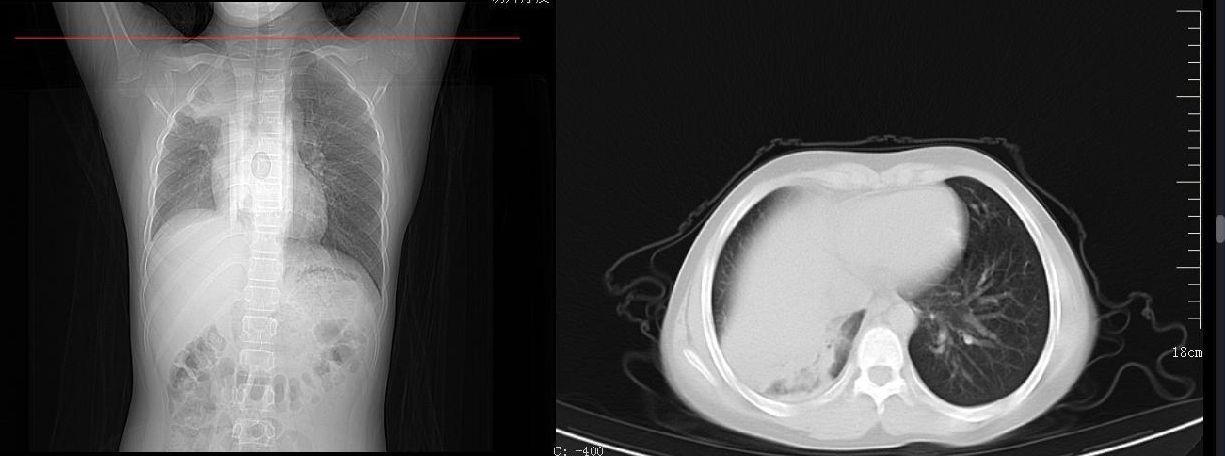

肺部ct显示,舟舟一侧肺部组织大面积变白。

接诊的儿科主任张雪荣经过一系列的查体后初步判断,舟舟已经发展成肺炎了。“收治入院后查胸片显示,孩子右肺内带见片状软组织样高密度影,右肺野内亦可见片状高密度影,右侧肋膈角变浅变钝,膈面模糊。考虑右肺部分不张伴胸腔积液可能。”看到胸片上舟舟的一侧肺部组织大面积变白后,家长既自责又后悔。好在经中西医结合治疗后,舟舟目前的症状已经明显好转。